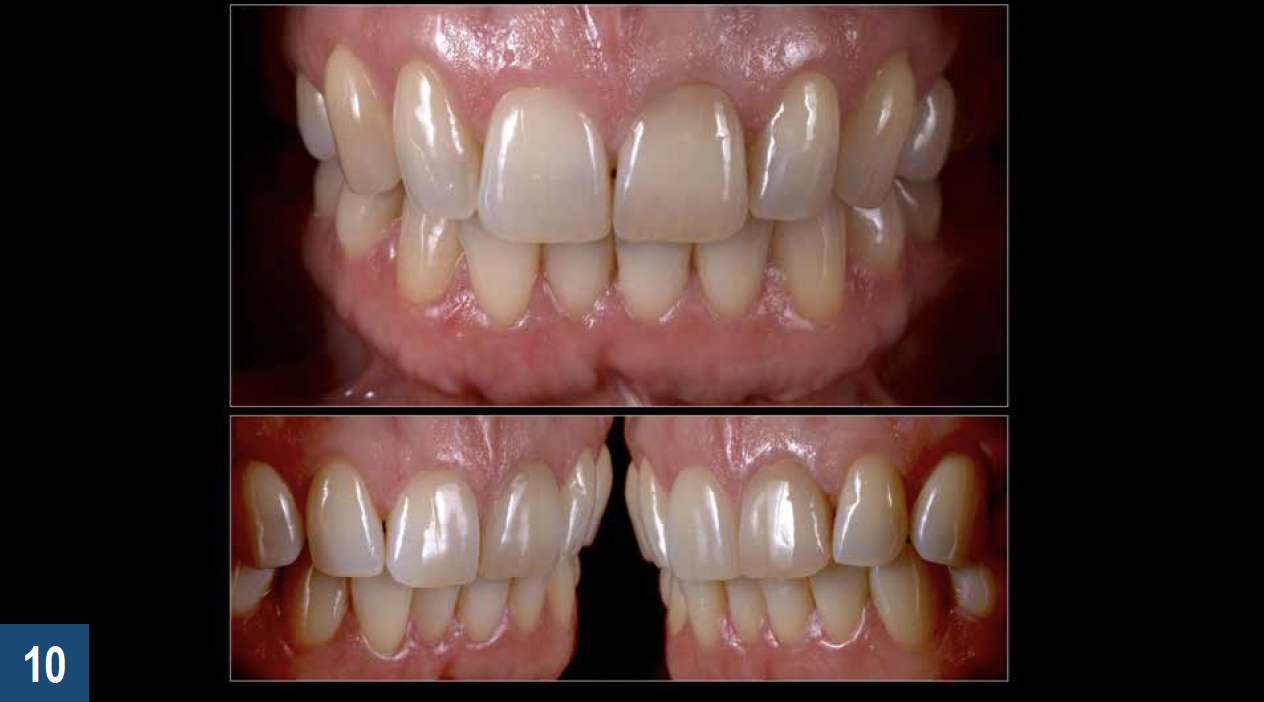

For clinical situations involving a nonvital and discolored natural tooth (Figure 10), intracoronal bleaching, also known as the "walking bleach" technique, has been consistently shown to be a conservative treatment option compared with more aggressive direct/indirect restorative procedures such as composite bonding, porcelain laminate veneers, or full coverage crowns.33Additionally, for patients requesting the lightening of a single dark tooth, internal bleaching is often more cost-effective and less dependent on patient compliance than the daily use of a whitening tray. Contemporary protocols often include the use of strong oxygen-releasing chemical compounds, such as 30% to 35% hydrogen peroxide, which have been associated with adverse complications including external invasive cervical root resorption.34,35 The evaluation and outcomes of endodontic techniques utilizing a safer 10% carbamide peroxide formulation are well-documented in the literature and clinically, and have proved to be a reliable, predictable option for the internal bleaching of nonvital discolored teeth (Figure 11).36-38

Fig 10. Discoloration of a nonvital single central incisor is a common clinical situation that can be addressed through a safe and conservative approach utilizing an internal bleaching technique (the “walking bleach” technique) with 10% carbamide peroxide (Pola Night, SDI).

Figure 10